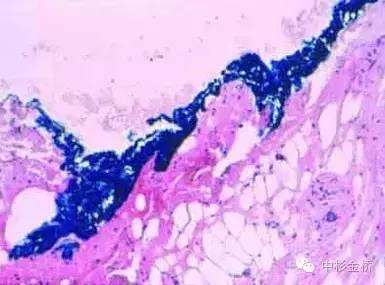

3、應(yīng)用于脂肪組織時(shí),可用噴壺噴灑少量丙酮對組織表面進(jìn)行脫脂處理,擦拭干后再使用色標(biāo)劑進(jìn)行染色。尤其適用于乳腺和皮下組織。

5、染色后組織可用福爾馬林固定或冷凍切片。